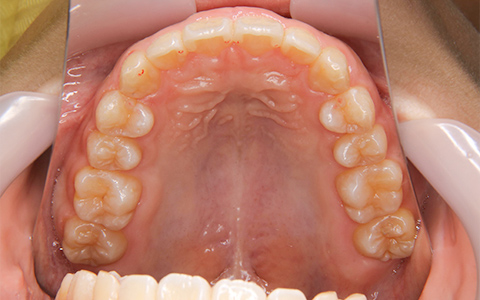

埋伏歯の位置や方向が確認できる

CT検査の例

CT検査で確認できる軸位断図

CTを使用すると、左記の軸位断図のように様々な角度の断面から歯の位置などの確認をすることができます。